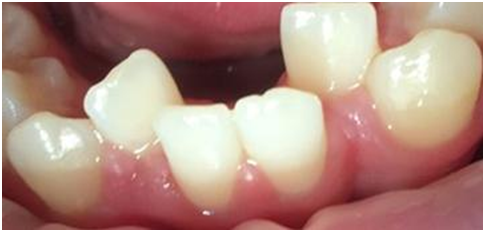

The second case (Figure 3) displays moderately malpositioned mandibular anterior teeth and essentially illustrates the method and apparatus for the restoration of alveolar bone morphology. The patient presented to a FASTBRACES® provider's private practice with a chief complaint of unfavorable esthetic appearance as it relates to moderate alveolar bone hypoplasia or Orthodontosis™ labial to the lingually displaced mandibular incisors roots. This results in a deficiency of alveolar bone labial to the central incisor that demonstrates the gingival recession. The treatment objectives, in this case, are to restore the morphology of alveolar bone around the malpositioned teeth which in turn will allow for new bone to cover the recession.

Figure 3 Before Maxillary and Mandibular Orthodontosis™ and Orthodontitis™ of anterior teeth with localized severe gingival recession, (Courtesy of Dr. Patrick Assal, Lausanne Switzerland).